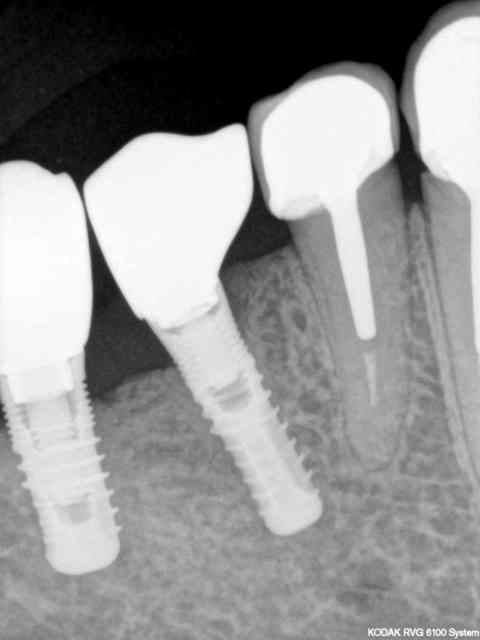

votre avis sur un cas vu today

le Monsieur veut absolument une solution fixe

14344 pano ecglox - Eugenol

14344 scan dm4wdw - Eugenol

t'as vu la gueule du sinus ....... il c'est passé quoi ?

Alvéolectomie à la fraise résine ?????

Tumeur ?

dis nous en un peu plus

dixit le patient: "j'ai eu des dents arrachées il y a une quinzaine d'années avec une grosse infection et des kystes et j'ai eu une communication avec le sinus"

pour remplacer de 22 à 26 j'ai 38 mm d'arcade soit 22-23-24-25 et une 3ème prémolaire.

pour 22-23 hauteur osseuse ok, un petit manque en épaisseur pour 23, pour les prémolaires faudrait que la cavité remplie de tissu mou soit ossifiée.

- dissection sous la muqueuse vestibulaire et sous le sinus avec curetage complet de la cavité et rerait du petit bout de racine résiduel

- membrane sous le sinus, comblement de la cavité et membrane en vestibulaire

- attente d'ossification

- implantation

çà risque d'être très chaud quand même (la dissection et le curetage complet dans les petits recoins)

vos avis?